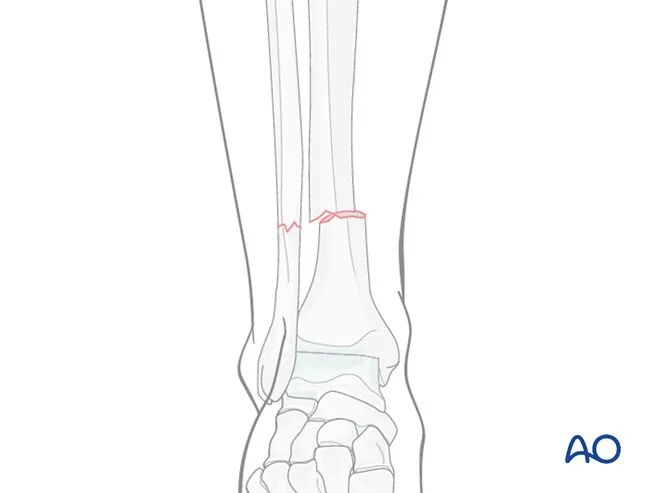

适应证

加压接骨板可用于治疗胫骨的任何横行骨折、两部分骨折。

该术式尤其适用于骨骺未闭合的儿童骨干骨折,此类骨折往往存在明显移位,且需达到解剖复位。

对于闭合复位可实现解剖复位的选择性横行骨折,可采用微创接骨术(MIO) 技术。

若软组织条件尚可耐受手术及植入物尺寸,谨慎采用微创接骨术可实现加压接骨板固定;此类情况下,骨膜下接骨板置入术的安全性优于皮下置入术。